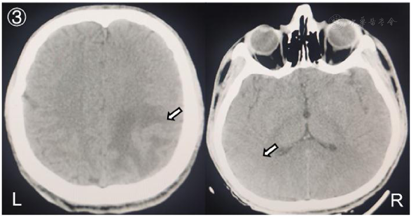

入院后给予脱水降颅压、低分子肝素桥接华法林抗凝、丙戊酸钠抗癫痫、床旁肢体康复等治疗措施,控制INR在2~3之间,患者意识逐步恢复清醒,认知功能未见明显障碍,头痛症状明显缓解,未见肢体抽搐等症状发作,右侧肢体功能明显改善,肌力恢复至5-级,复查头颅CT(2020年11月19日)提示:左侧额叶、右侧颞叶出血灶较前吸收减少(图3);头颅MRV(2021年12月5日):右侧横窦纤细,乙状窦部分显示不清,上矢状窦管壁毛糙、粗细不均,对比前片有所缓解(图4)。